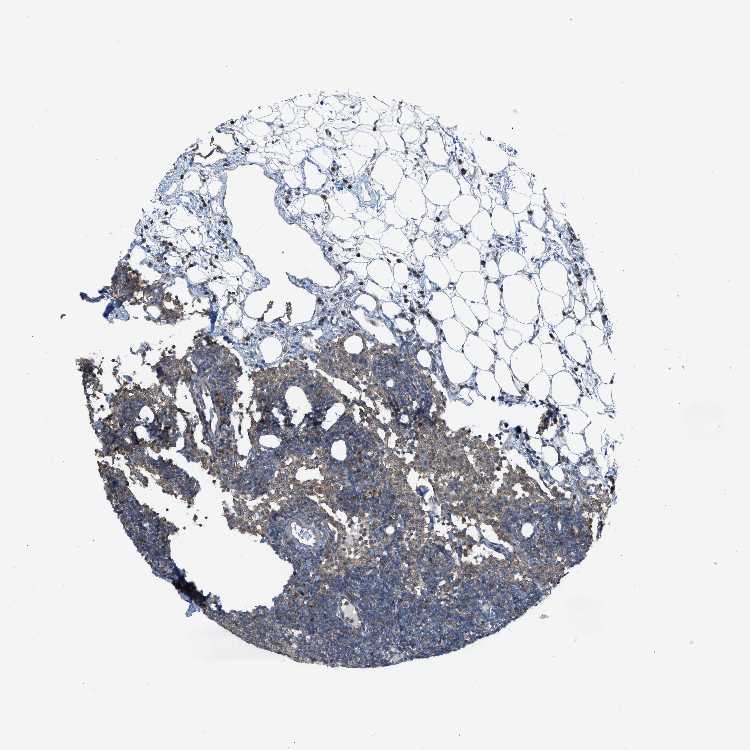

TISSUE PRIMARY DATA LYMPH NODE Show tissue menu

Lymph node

LYMPH NODE - Antibody stainingi

Antibody staining in the annotated cell types in the current human tissue is reported as not detected, low, medium, or high, based on conventional immunohistochemistry profiling in selected tissues. This score is based on the combination of the staining intensity and fraction of stained cells.

Each image is clickable and will lead to virtual microscopy that enables deeper exploration of all samples and also displays staining intensity scores, fraction scores and subcellular localization as well as patient and tissue information for each sample.

Antibody HPA020994Antibody HPA020996Antibody CAB005035

Germinal center cells MediumMediumNot detected

Non-germinal center cells LowHighNot detected